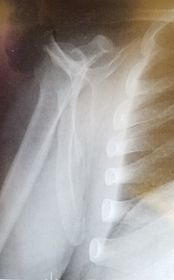

| AP Humerus | humeral epicodyles not in profile radial head, neck and tuberosity to not superimpose ulna arm is externally rotated (greater tubercle in profile) |

| Lateral Humerus | over rotation places the humeral head within the field of the chest |

| Lateral Humerus | epicondyles are not perpendicular humerus is internally rotated (lesser tubercle is in profile medially) overrotation |

| AP Humerus | ANATOMY: entire humerus: shoulder -> elbow CRITERIA: greater tubercle in profile - hand externally rotated humeral epicondyles are parallel to IR POSITIONING: CR perpendicular @ midhumerus |

| Lateral Humerus | ANATOMY: entire humerus: shoulder -> elbow CRITERIA: lesser tubercle in profile - arm internally rotated epicondyles superimposed POSITIONING: pt rotated 15-20 degrees from PA to get arm lateral and away from chest - flex elbow 90 degrees CR perpendicular @ midhumerus |